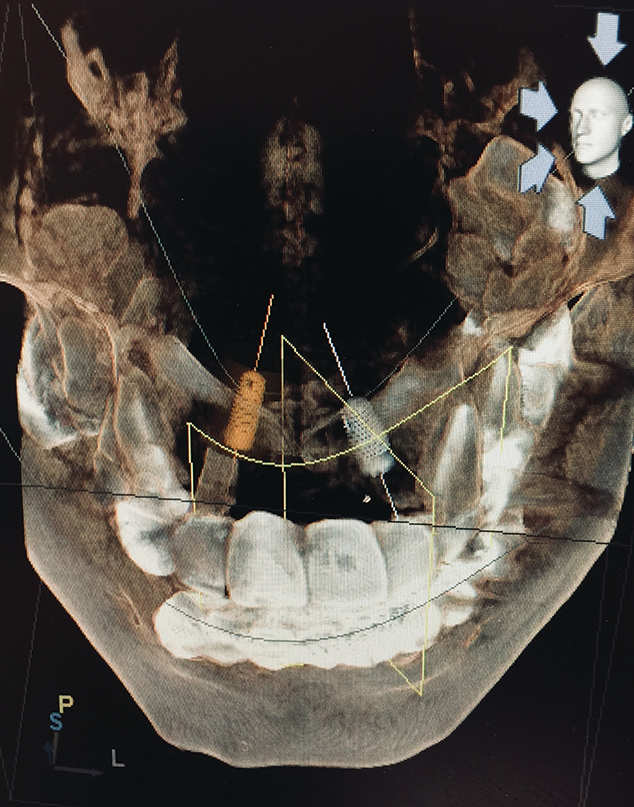

Digital imaging—whether traditional 2-D imaging with sensors, phosphor plates, or 3-D cone beam images— provides dental professionals and patients with diagnostic capabilities that previously were unimagined. Cone beam computed tomography (CBCT) has revolutionized dental imaging by bringing in the third dimension of imaging. Traditional 2-D imaging provides only height and width, while 3-D imaging provides the depth.3 Two-dimensional imaging is good for diagnosing simple concerns, while 3-D imaging lends itself to more in-depth diagnosis and use in complex treatment planning. Digital imaging combined with intraoral photography assists teams in increasing patient case acceptance. The old adage, “A picture is worth a thousand words,” is so true in today’s digitally enhanced practice. Patients understand and can take ownership of their health when they see the effects of disease. They can be involved in the results of care rather than just being told about it or viewing issues on small black-and-white images.